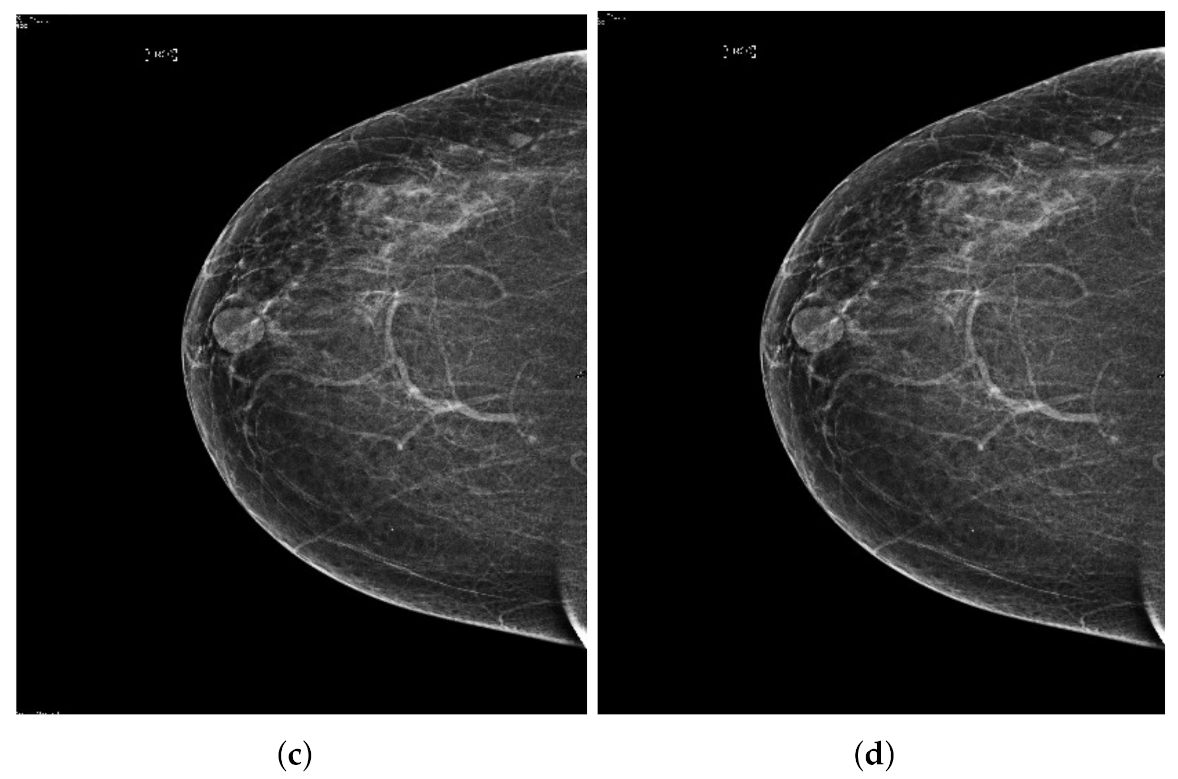

Figure 12.

Analysis of MLO view of BI-RADS-3 mammogram images.